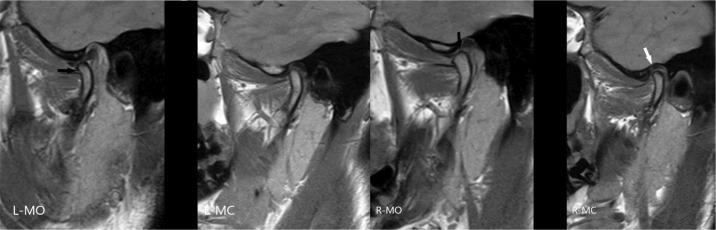

Images of Temporomandibular Joint Arthropathy in Patient with Severe Hemophilia B with Inhibitor and Patient with Type III von Willebrand Disease with Inhibitor

一名严重血友病 B 型患者(含抑制剂)和一名 III 型 Von Willebrand 患者(含抑制剂)的颞下颌关节关节病图像。